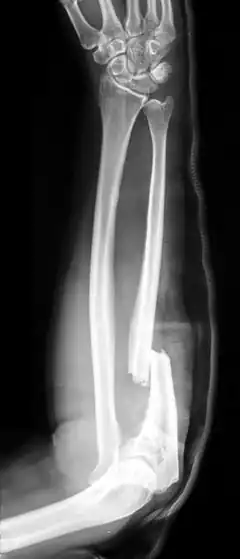

Une lésion défensive est un type de lésion, généralement une blessure, témoignant d'une attitude défensive de la victime au moment où elle l'a subie. Les lésions défensives constituent des indices importants dans le cadre de certaines enquêtes de police car elles établissent, lorsqu'elles sont dûment constatées par la médecine légale, l'existence d'une agression physique, ce qui permet d'écarter certains scénarios. Ainsi, la présence de coupures à l'avant-bras d'un cadavre peut témoigner de la tentative, de la part du meurtrier, de porter à la tête de sa victime des coups à l'arme blanche, écartés par réflexe. Cela autorise ensuite l'établissement d'hypothèses quant au profil du criminel.